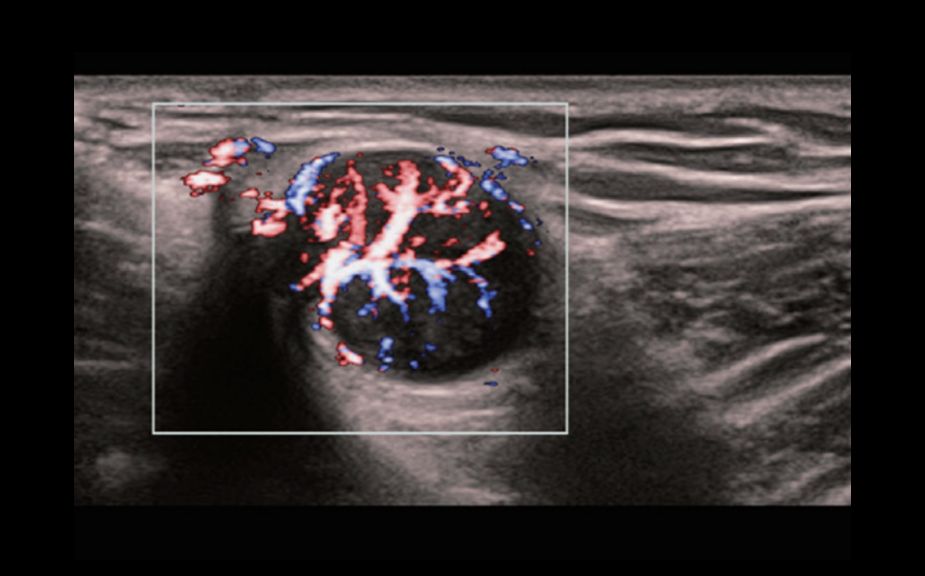

–Ě–ĺ–≤–Ķ–Ļ—ą–ł–Ļ –Ņ–ĺ–ī—Ö–ĺ–ī –ļ –ł–∑—É—á–Ķ–Ĺ–ł—é —Ā–ĺ—Ā—É–ī–ł—Ā—ā–ĺ–Ļ –≥–Ķ–ľ–ĺ–ī–ł–Ĺ–į–ľ–ł–ļ–ł: V Flow

–ė—Ā–Ņ–ĺ–Ľ—Ć–∑—É—é—ā—Ā—Ź –ľ–į—Ä–ļ–ł—Ä–ĺ–≤–į–Ĺ–Ĺ—č–Ķ —Ü–≤–Ķ—ā–ĺ–ľ –≤–Ķ–ļ—ā–ĺ—Ä–į –ī–Ľ—Ź –ł–Ĺ–ī–ł–ļ–į—Ü–ł–ł –∑–Ĺ–į—á–Ķ–Ĺ–ł—Ź —Ā–ļ–ĺ—Ä–ĺ—Ā—ā–ł –ł –Ĺ–į–Ņ—Ä–į–≤–Ľ–Ķ–Ĺ–ł—Ź –ī–≤–ł–∂–Ķ–Ĺ–ł—Ź –ļ–Ľ–Ķ—ā–ĺ–ļ –ļ—Ä–ĺ–≤–ł. –Ď–Ľ–į–≥–ĺ–ī–į—Ä—Ź —Ā–≤–Ķ—Ä—Ö–≤—č—Ā–ĺ–ļ–ĺ–Ļ —á–į—Ā—ā–ĺ—ā–Ķ –ļ–į–ī—Ä–ĺ–≤ V Flow –ĺ–Ī–Ķ—Ā–Ņ–Ķ—á–ł–≤–į–Ķ—ā —á—Ä–Ķ–∑–≤—č—á–į–Ļ–Ĺ–ĺ —á–Ķ—ā–ļ—É—é, —ā–ĺ—á–Ĺ—É—é –ł –Ĺ–Ķ–∑–į–≤–ł—Ā–ł–ľ—É—é –ĺ—ā —É–≥–Ľ–į –ļ–ĺ–ľ–Ņ–Ľ–Ķ–ļ—Ā–Ĺ—É—é –ĺ—Ü–Ķ–Ĺ–ļ—É —Ā–ĺ—Ā—É–ī–ł—Ā—ā–ĺ–Ļ –≥–Ķ–ľ–ĺ–ī–ł–Ĺ–į–ľ–ł–ļ–ł —Ā –≤–ĺ–∑–ľ–ĺ–∂–Ĺ–ĺ—Ā—ā—Ć—é –≤—Ā–Ķ—Ā—ā–ĺ—Ä–ĺ–Ĺ–Ĺ–Ķ–≥–ĺ –į–Ĺ–į–Ľ–ł–∑–į.

V Flow

–Ě–ĺ–≤–Ķ–Ļ—ą–ł–Ļ –Ņ–ĺ–ī—Ö–ĺ–ī –ļ –ł–∑—É—á–Ķ–Ĺ–ł—é —Ā–ĺ—Ā—É–ī–ł—Ā—ā–ĺ–Ļ –≥–Ķ–ľ–ĺ–ī–ł–Ĺ–į–ľ–ł–ļ–ł: V Flow

–ė—Ā–Ņ–ĺ–Ľ—Ć–∑—É—é—ā—Ā—Ź –ľ–į—Ä–ļ–ł—Ä–ĺ–≤–į–Ĺ–Ĺ—č–Ķ —Ü–≤–Ķ—ā–ĺ–ľ –≤–Ķ–ļ—ā–ĺ—Ä–į –ī–Ľ—Ź –ł–Ĺ–ī–ł–ļ–į—Ü–ł–ł –∑–Ĺ–į—á–Ķ–Ĺ–ł—Ź —Ā–ļ–ĺ—Ä–ĺ—Ā—ā–ł –ł –Ĺ–į–Ņ—Ä–į–≤–Ľ–Ķ–Ĺ–ł—Ź –ī–≤–ł–∂–Ķ–Ĺ–ł—Ź –ļ–Ľ–Ķ—ā–ĺ–ļ –ļ—Ä–ĺ–≤–ł. –Ď–Ľ–į–≥–ĺ–ī–į—Ä—Ź —Ā–≤–Ķ—Ä—Ö–≤—č—Ā–ĺ–ļ–ĺ–Ļ —á–į—Ā—ā–ĺ—ā–Ķ –ļ–į–ī—Ä–ĺ–≤ V Flow –ĺ–Ī–Ķ—Ā–Ņ–Ķ—á–ł–≤–į–Ķ—ā —á—Ä–Ķ–∑–≤—č—á–į–Ļ–Ĺ–ĺ —á–Ķ—ā–ļ—É—é, —ā–ĺ—á–Ĺ—É—é –ł –Ĺ–Ķ–∑–į–≤–ł—Ā–ł–ľ—É—é –ĺ—ā —É–≥–Ľ–į –ļ–ĺ–ľ–Ņ–Ľ–Ķ–ļ—Ā–Ĺ—É—é –ĺ—Ü–Ķ–Ĺ–ļ—É —Ā–ĺ—Ā—É–ī–ł—Ā—ā–ĺ–Ļ –≥–Ķ–ľ–ĺ–ī–ł–Ĺ–į–ľ–ł–ļ–ł —Ā –≤–ĺ–∑–ľ–ĺ–∂–Ĺ–ĺ—Ā—ā—Ć—é –≤—Ā–Ķ—Ā—ā–ĺ—Ä–ĺ–Ĺ–Ĺ–Ķ–≥–ĺ –į–Ĺ–į–Ľ–ł–∑–į.

V Flow